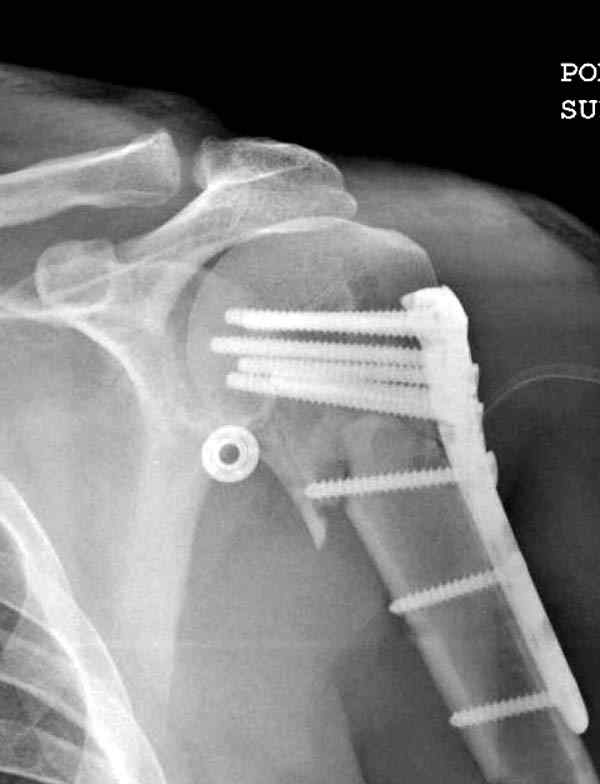

Здесь пример открытой репозиции 57 летнего с переломом плеча (1,2) смещение обнаружено на интероперационном снимке. При нормальной прямой проекция (3) угловое смещение обнаружили в аксиальной проекции (4)

После устранения смещения пластина установлена выше (5,6,7) и финальные снимки (8,9,10)

Подбор импланта тоже имеет значение, например многие импланты направлены для фиксации перелома без учета ротаторной манжетки. Предпочтительными являются низко сидящие полиаксиальные пластины, где верхние шурупы можно проводить под углом в 120 градусов. (11)

Пластина от Synthes или ее копии (надеюсь простят критику друзья из Деоста) считаются трудным из-за обширности доступа, особенно при установке верхне-заднего шурупа, где доступ надо расширять в верхнем отделе до ротаторной манжетки. Верхне сидящие импланты предназначены для проведения опоры (buttress) за бугристость плеча, но тогда приходится сталкиваться с подакромиальным импинжментом.

дополнительные снимки по протезированию